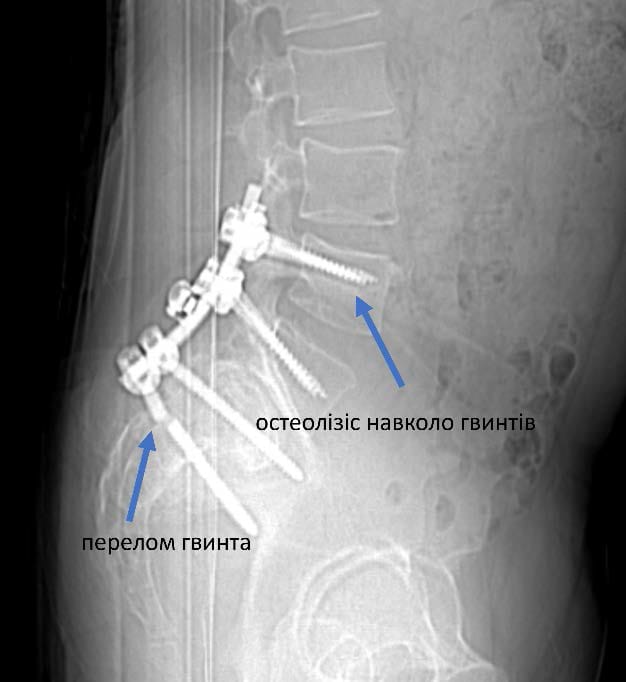

Усі повторні операції пов’язані з більшим ризиком ускладнень та потребують ретельного планування. «З одного боку це був цікавий випадок. З іншого – ми завжди допомагаємо нашим військовим з особливим задоволенням», - розповідає Олексій Леонтьєв. Склалося так, що у пацієнта було встановлено 6 гвинтів, з яких 1 поламався, 3 розхиталося і таким чином його хребет втратив опороздатність. Складність операції полягала і ще у тому, що зламану частину гвинта видалити практично неможливо і ставало питання про встановлення додаткових гвинтів та видалення тих що розхиталися. План був складений. На допомогу прийшли наші колеги (https://www.facebook.com/Implants.in.ua), які надали металоконструкцію, що була необхідна для пацієнта.

Це була складна операція. Вона тривала 7 годин. Розхитані та поломані гвинти було видалено, а також конструкцію було додатково укріплено ще гвинтами. Перепроведено тазовий гвинт. Також була виконана декомпресія корінця S1 що давав виражений больовий синдром.

Результати реоперації на наступних малюнках: